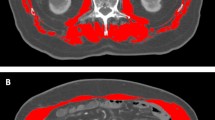

Imaging analysis of skeletal muscle mass

CT images of patients taken within one week prior to DEB-TACE operation were utilized for quantifying skeletal muscle mass at the level of the third lumbar vertebra (L3). The skeletal muscle index (SMI, cm2/m2) was employed to evaluate the status of skeletal muscle quality, which is determined by calculating the square of skeletal muscle area (cm2) divided by the square of height (m2)19. The images were analyzed by two trained radiologists, G.F.Z. and C.S.Z., who have 25 and 31 years of imaging experience, respectively. Tomovision SliceOmatic version 4.3 software (Toronto, Canada) were used to delineate the area of interest of the skeletal muscle on axial CT at the middle of the L3 vertebral body (Fig. 1). The muscles include the psoas, rectus, transverse abdominis, quadratus lumborum, internal obliques, longissimus pectoralis, and pectoral spinous muscles. The entire muscle area was measured, and the average of the two radiologists’ measurements was calculated for subsequent analysis.